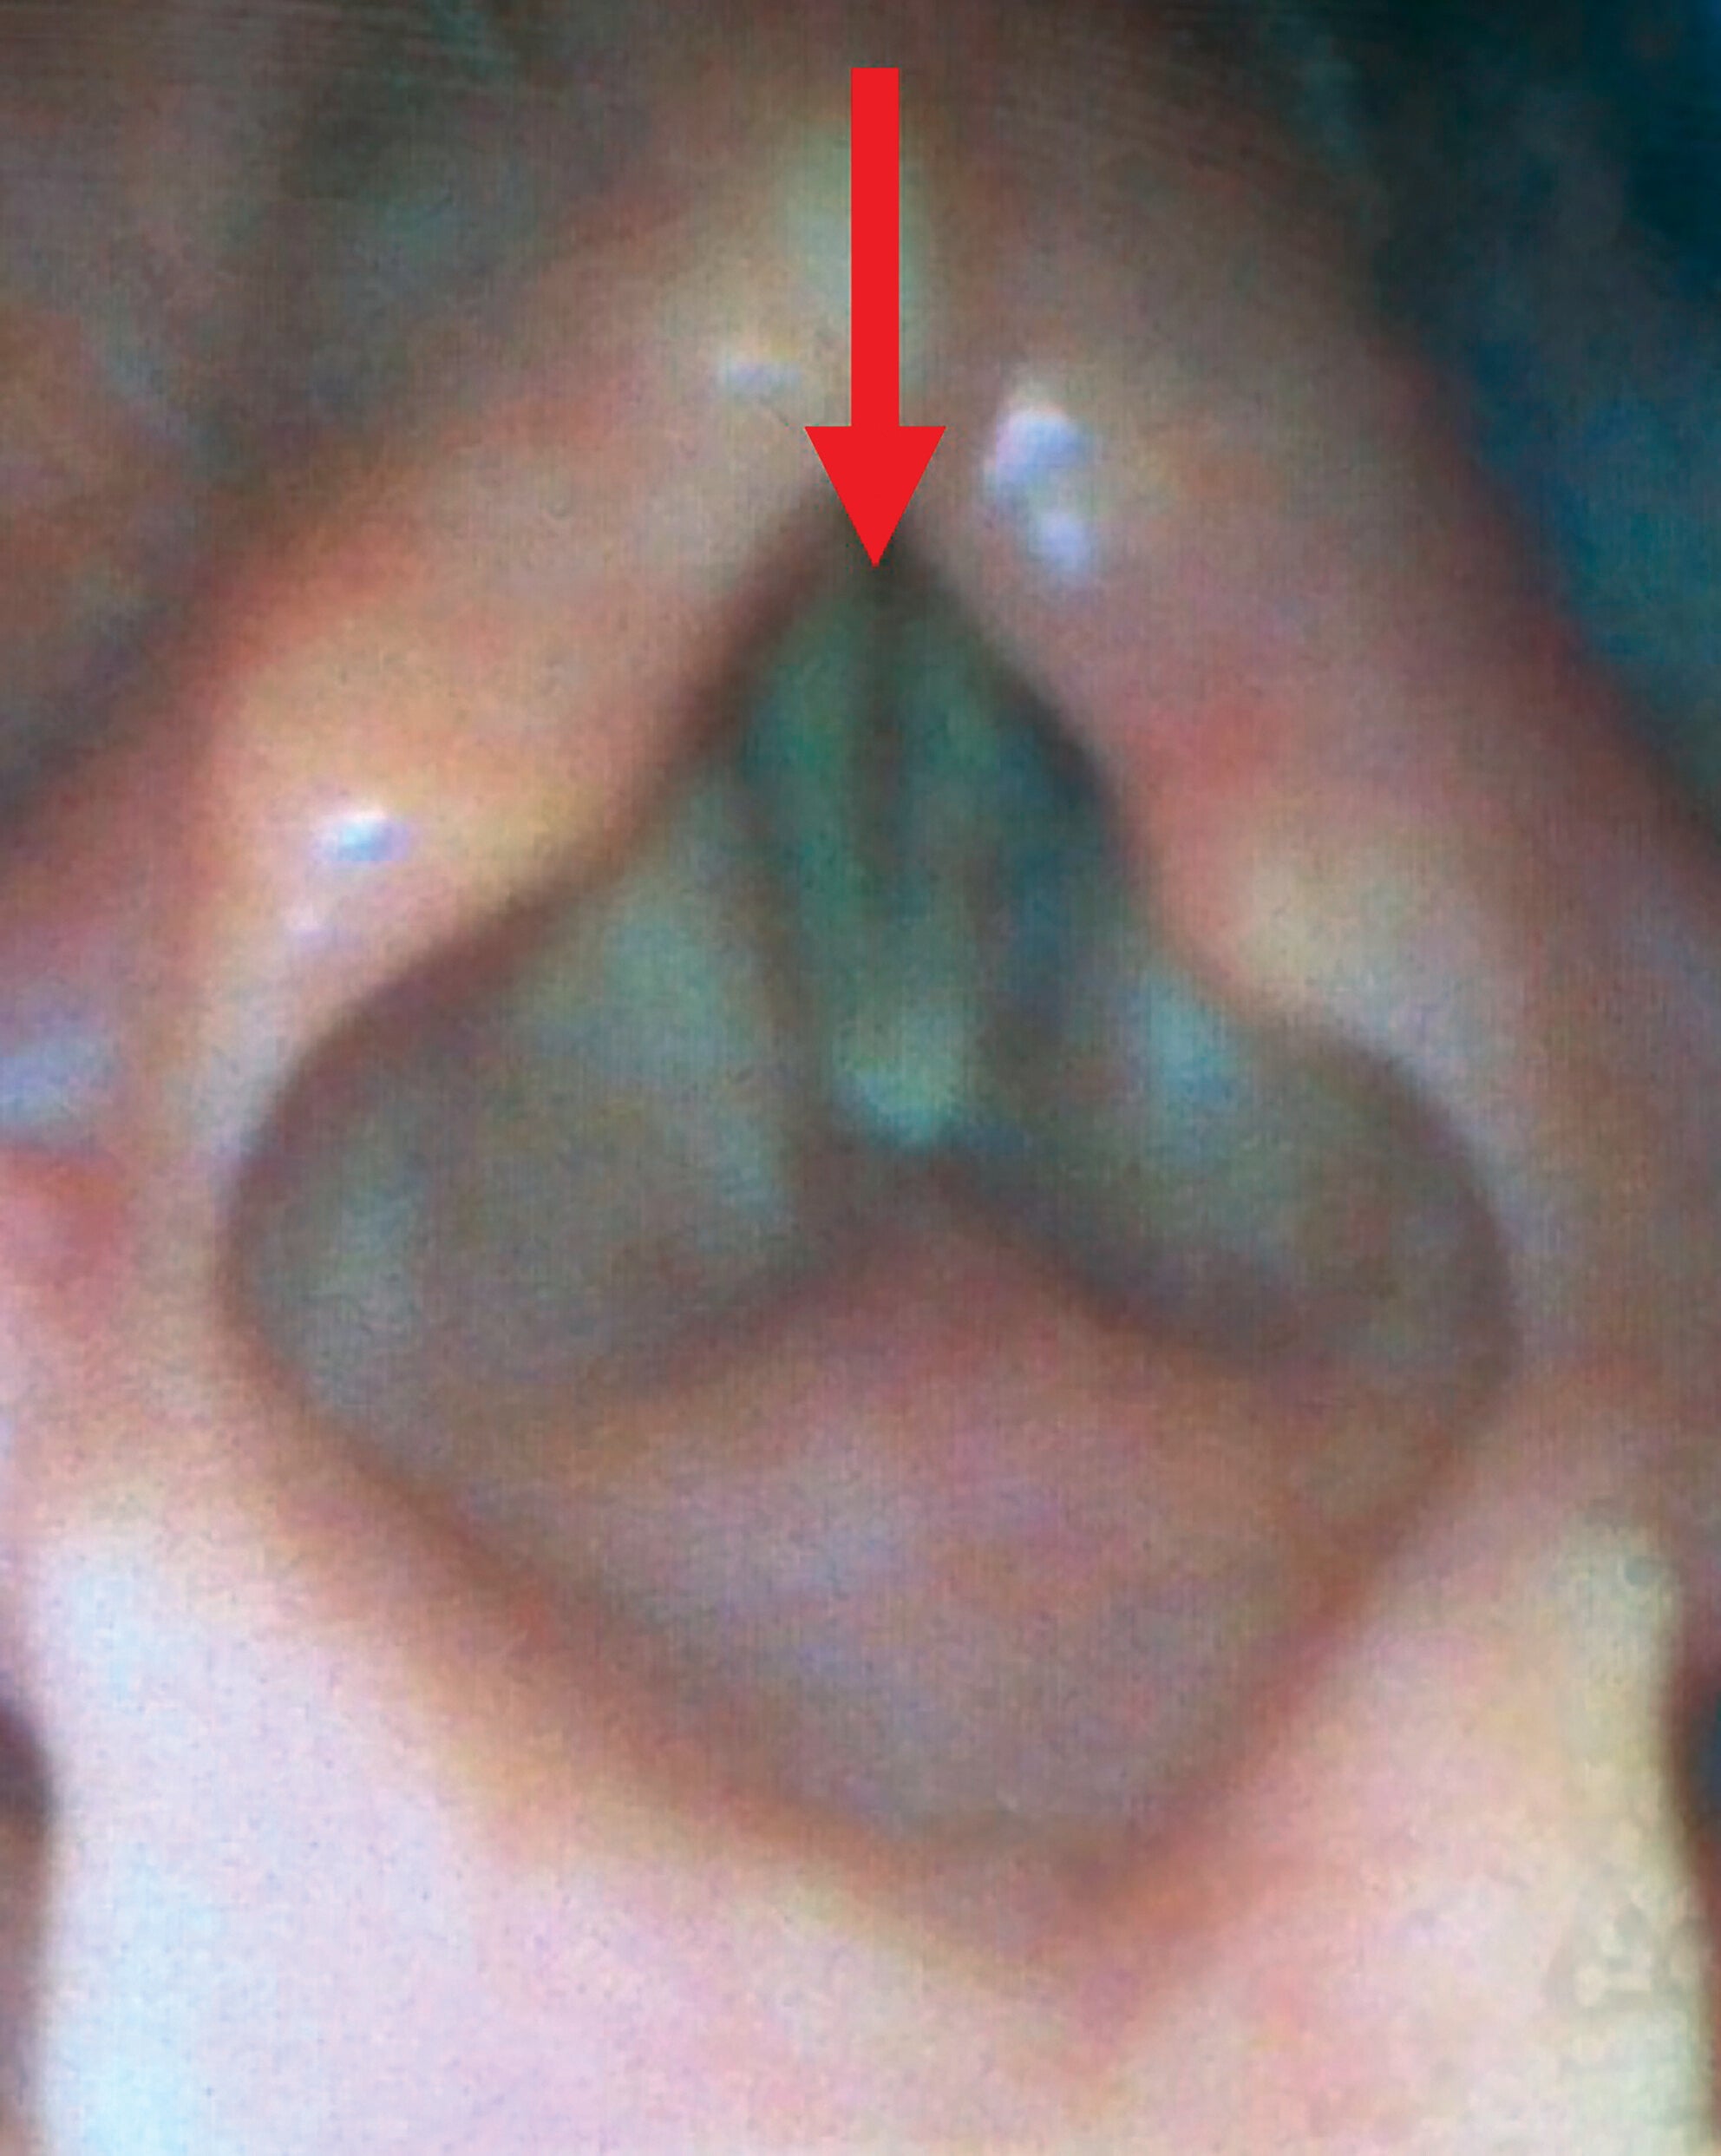

Figure 1. Vocal fold visualization as seen on bedside laryngoscopy. Arrow shows the maximal glottic opening due to bilateral vocal fold paralysis

A 73-year-old woman with a recent upper respiratory tract infection presented to the emergency department (ED) with three days of progressive dyspnea and stridor. Bedside laryngoscopy revealed bilateral vocal fold paralysis (Fig. 1). The patient decompensated in the ED, requiring subsequent intubation and transfer to the ICU, with tracheotomy placement planned for the next day for airway stabilization. Bedside clinical examination of the neck in the ICU was unremarkable, and the patient was taken to the operating room.